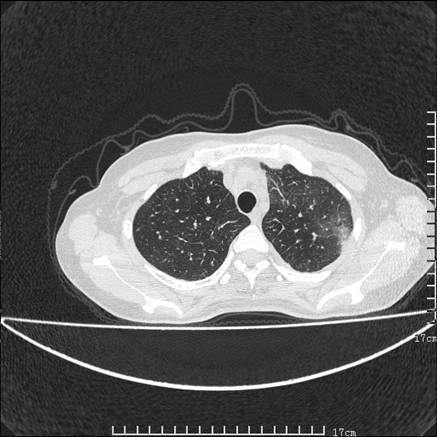

女,46岁,患胃溃疡多年,溃疡大小约1.0cm左右,后于5年前手术,病理为胃癌。主诉:半月前感冒后胸闷,气短,有咳嗽,无明显咳痰,无发热。偶有腰背部不适。

以下为高分辨扫描图像

双肺小叶间增厚,双肺散布粟米影和磨玻璃状影,以双肺上叶为重。结合病史考虑转移(癌性淋巴细管炎)可能性大。

结合病史:认为是典型肺部癌性淋巴管炎、淋巴结转移。请看图解。

正如caihe主任所言,影像表现结合临床病史应该支持肺癌性淋巴管炎;上肺大片边缘不清的渗出病变,多系感染所致,临床有感冒病史并咳嗽表现。肺癌性淋巴管炎临床一般无咳嗽、咳痰症状。

肺癌性淋巴管炎征象分为主要征象及合并征象,主要征象包括:

1、近肺门支气管血管周围间质结节状增厚;

2、小叶间隔结节状增厚;

3、小叶中央间质结节状增厚;

4、胸膜下间质结节状增厚。

合并征象为:纵隔淋巴结增大,胸腔积液,肺多发随机分布的小结节等。